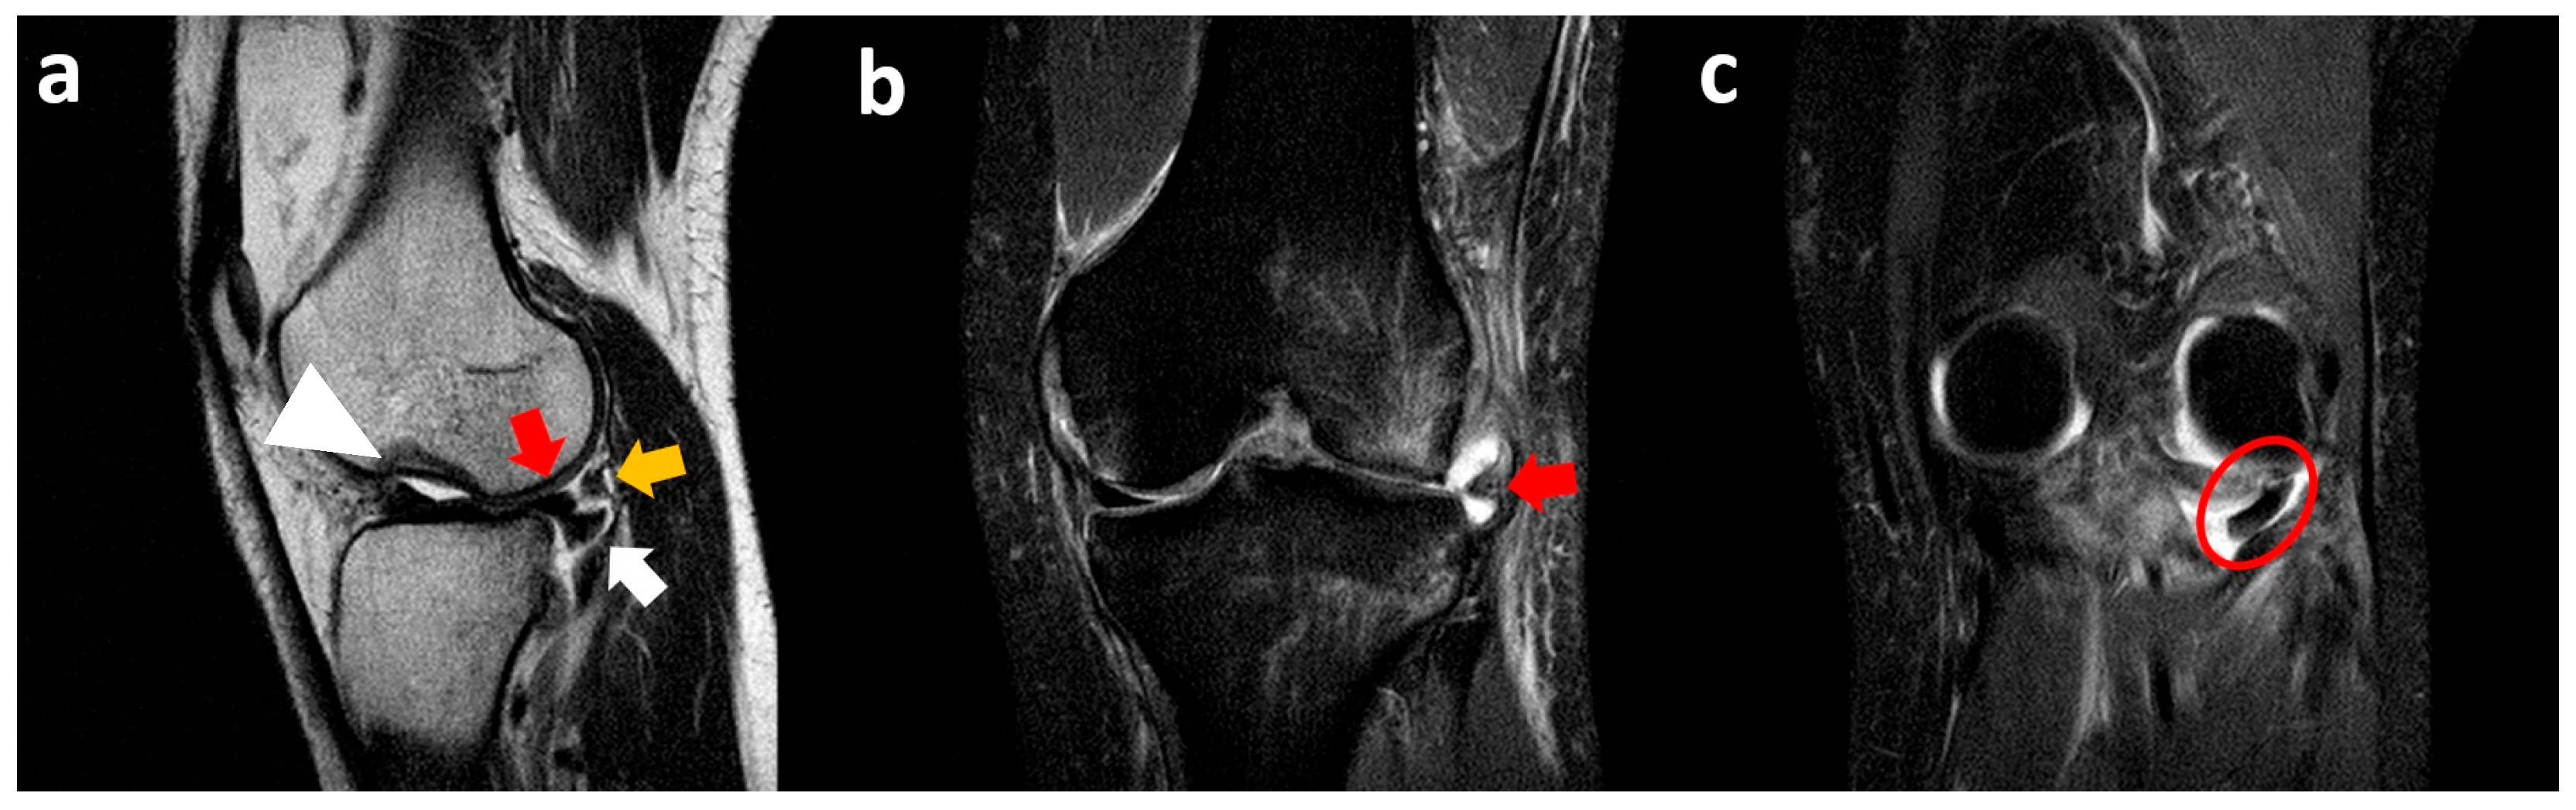

3.1. Medial Meniscus Flap Under the Medial Collateral Ligament